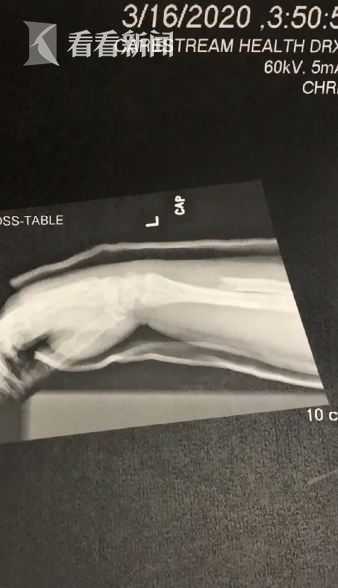

隨後,她也上傳了自己的X光照片、術後恢復照,並透過社交網路分享從負傷中恢復的情況,醫生為她打入1片鋼板與8個鋼釘,大約8周之後骨頭才癒合。